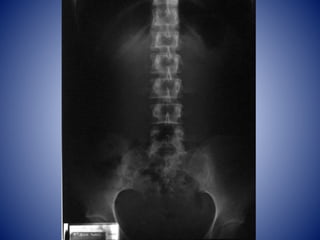

VERTEBRAS LUMBARES

• Cuerpos macizos, laminas robustas y ausencia

de fositas costales

• Orificios de ovalados a triangulares

• L5 es la mayor de todas las vertebras lumbares

y principal responsable del ángulo lumbosacro

SACRO

• Hueso grande en forma de cuña triangular

• 5 vertebras sacras fusionadas en los adultos

• Forma parte de los huesos de la cadera

• Techo y pared postero superior de la parte

posterior de la cavidad pélvica

• Otorga fortaleza y estabiliza pelvis

• Conducto sacro: raíces nerviosas cola de caballo

• Promontorio sacro